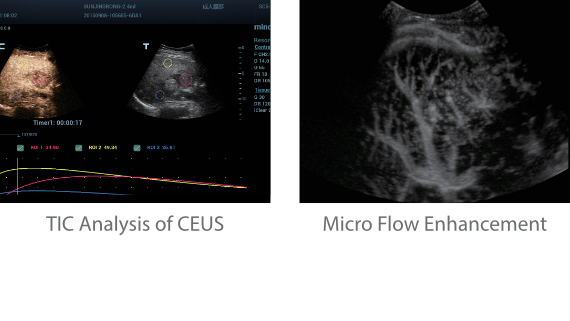

Neben der erstklassigen Bildqualit?t verbessert Resona 7 auch die klinischen Forschungsm?glichkeiten mit dem revolution?ren V Flow f├╝r die vaskul?re h?modynamische Bewertung und der intelligentesten Ebenenerfassung aus 3D-Datens?tzen f├╝r die f?tale ZNS-Diagnose. Mit der Kombination aus intuitiver, gestenbasierter Multi-Touch-Bedienung und allen wichtigen klinischen Funktionen ist das Resona 7 ein echter Wegbereiter f├╝r neue Ultraschall-Innovationen.

Die St?rken des Resona 7 sind bis ins kleinste Detail durchdacht. Seine erstklassige Bildqualit?t ist das Ergebnis einer erfolgreichen Fusion. Mindray und Zonare Medical Systems haben ihren Kernkompetenzen geb├╝ndelt, um ein Premiumsystem Wirklichkeit werden zu lassen. Dank der Vector Flow-Funktion k?nnen bei Gef??untersuchungen mehr als 400 Bilder pro Sekunde dargestellt werden. Somit entstehen ganz neue M?glichkeiten der Diagnose.